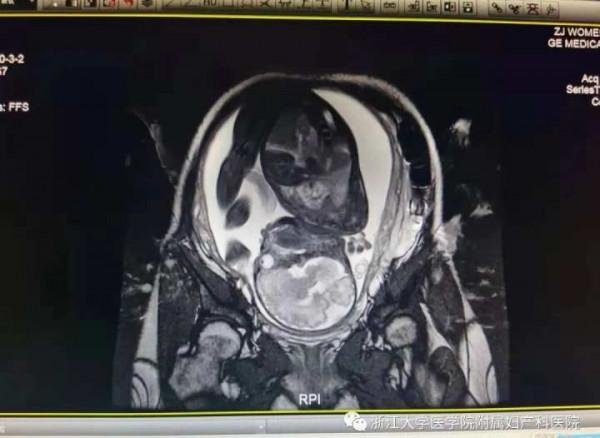

“上一次我們發稿時,靜靜應該是懷孕30周左右。之後,我們依然每週複查疤痕情況,看到疤痕厚度穩定在1.0毫米左右,以前向外膨出的情況沒有再次出現。B超監測寶寶的生長髮育情況,結果也是不錯的。32周時,我們又一次做了磁共振(MRI)來複查子宮疤痕的癒合情況。雖然提示下段依然菲薄,但羊膜囊未見膨隆,跟之前比有明顯好轉了。”團隊成員馮燕一直密切關注靜靜的情況,為了延長孕周努力著。